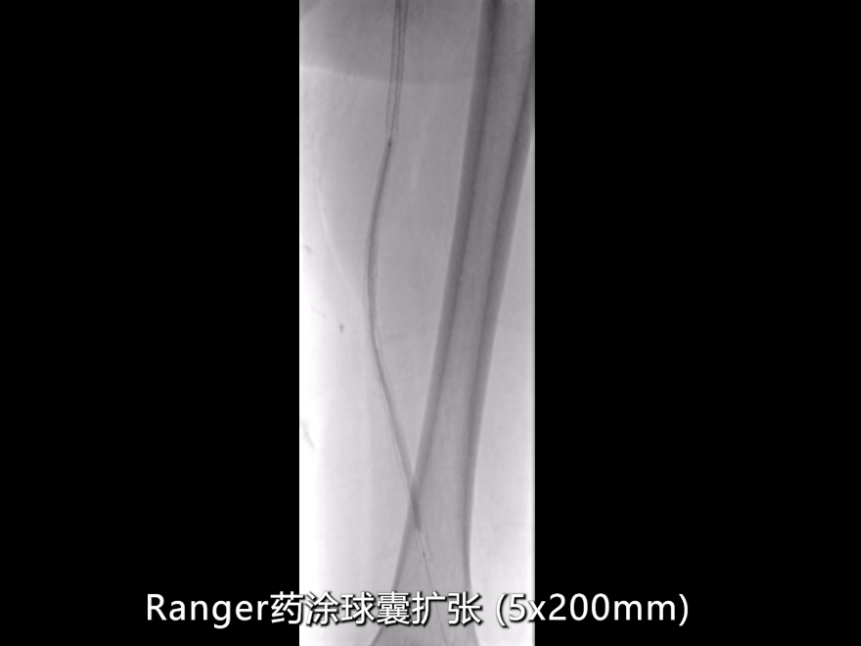

药物涂层球囊强化:

近端支架内病变采用5×200mmRanger药物涂层球囊扩张,强化抗再狭窄效果。